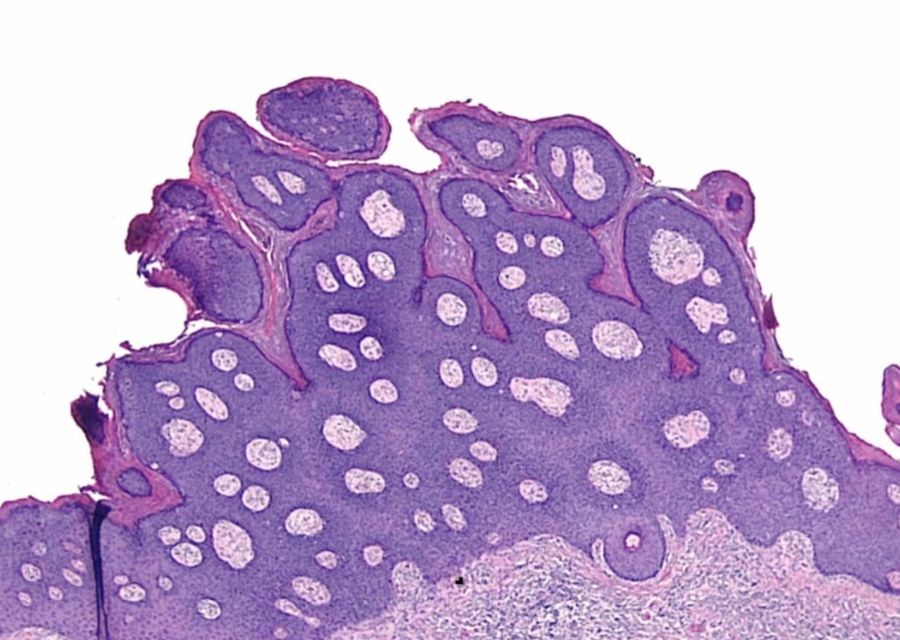

condyloma accuminatum:

Low mag: warts like

High mag: koilocytes, raisin like nucleus